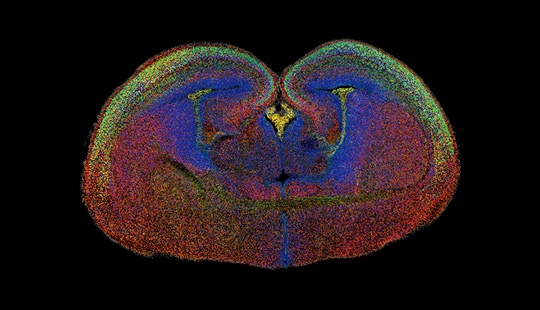

(3) 操作が簡単な光学セクショニング(光学切片)イメージング方式。プロジェクター素子を用いた構造化照明(Structured Illumination)により、標本を高速でスキャンします。レーザーではなくLED光源を使用するため、光退色を軽減し、幅広い波長域で蛍光のにじみがない高解像度画像を取得できます。BZシリーズは、画質が(共焦点顕微鏡に)ほぼ匹敵する一方で、撮像速度が速く、光毒性が低く、操作がより簡単です。

厚みのある標本でも、焦点面の情報を正確に検出し、鮮明な画像を取得できます。動物細胞、植物細胞、培養組織など、様々な標本を忠実に再現します。